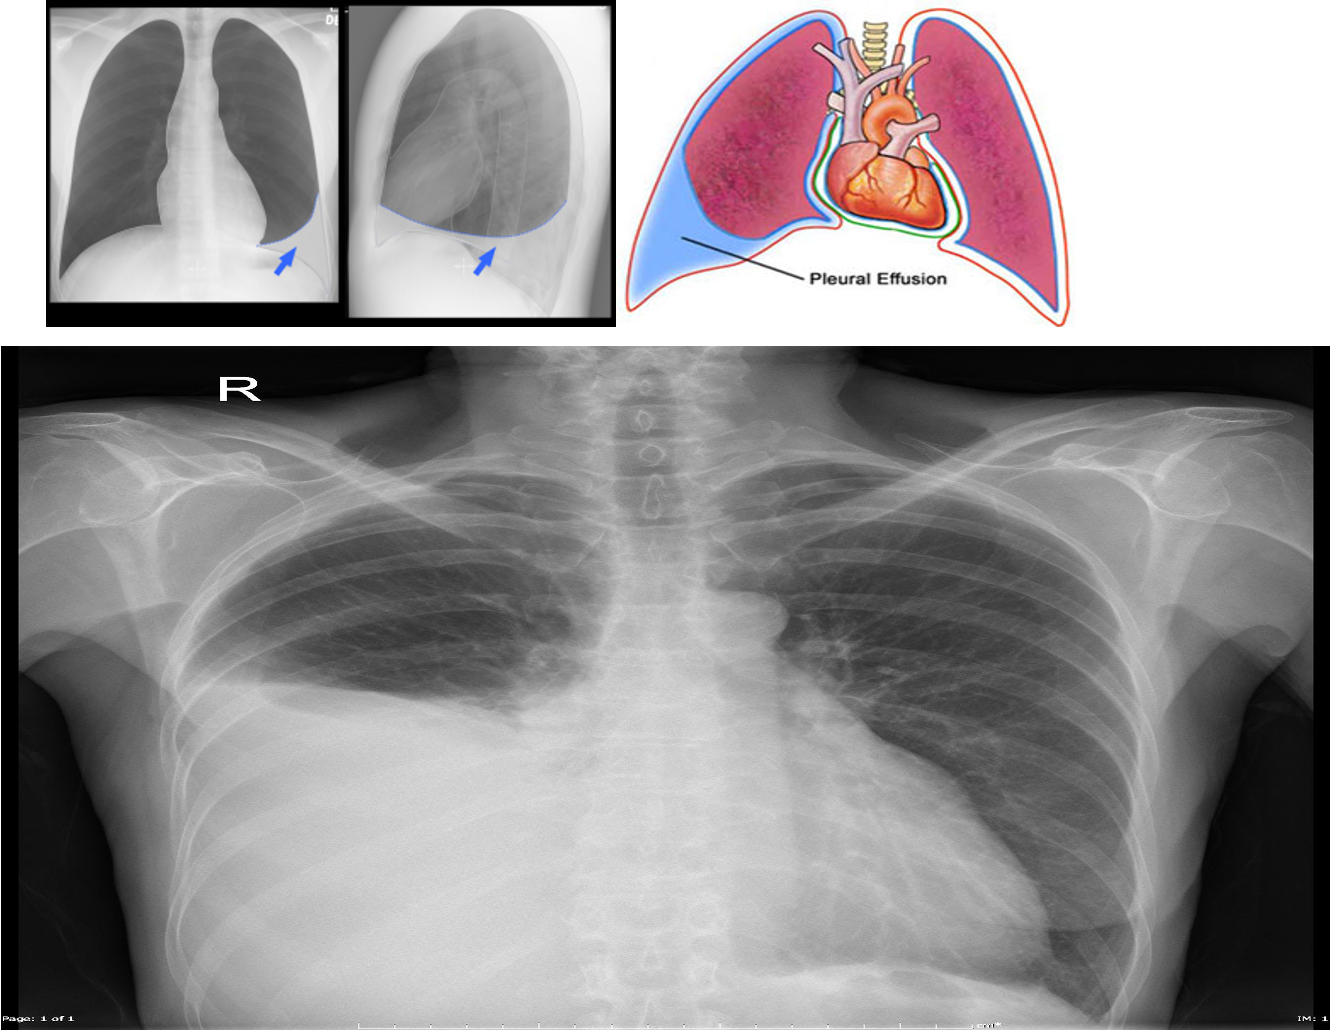

Chest X-ray: Lateral decubitus view (most sensitive): > 200 ml.

- Unilateral blunting of the costophrenic angle

- Homogeneous density with a meniscus-shaped margin (meniscus sign)

- Complete opacification of the lung (Large effusion) and Mediastinal shift and tracheal deviation.

Ultrasound: Quick, bedside assessment, if planning thoracentesis.